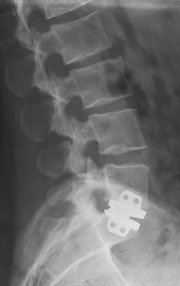

Diskusprotesebehandlingen afløser den konventionelle operationsmetode, der består i, at man fjerner den læderede bruskskive mellem hvirvlerne og i samme indgreb foretager en stabiliserende, stivgørende operation af hvirvelsøjlen. Hermed reduceres smerteintensiteten i et vist omfang, men der opnås ikke samme bevægelighed som ved behandling med diskus-protese.

Flere protese-designs har været anvendt. Det mest almindelige anvendte design i dag er protese med metal-backing med eller uden polyethylendel, ganske lig protese-designs anvendt i knækirurgien.

På markedet eksisterer der i dag fire forskellige protesetyper, som har udbredt anvendelse. Charité protesen var den første, der blev kommercielt tilgængelig, Prodisc er anvendt fra omkring 1990 og Maverick protesen fra Medtronic er fra ca. år 2000. Øvrige protesetyper er under udvikling og finder stigende anvendelse.